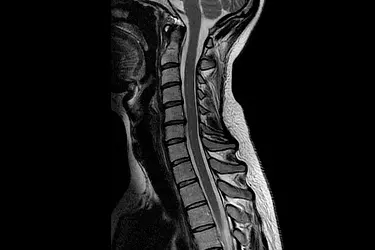

Brain & Spine MRI

Comprehensive head and spine examinations can be performed with dedicated programs. customized presets for fast scanning . The Neuro Suite also includes protocols for diffusion imaging, perfusion Neurology imaging, and Functional MRI. The MRI of spine lets your doctor examine the small bones, called vertebrae, which make up your spinal column, as well as the spinal discs, spinal canal and spinal cord. MRI scans of the spine are needed when conservative treatment is not working and more aggressive back pain treatments (e.g. spinal injections or surgery) are contemplated to relieve the symptoms.